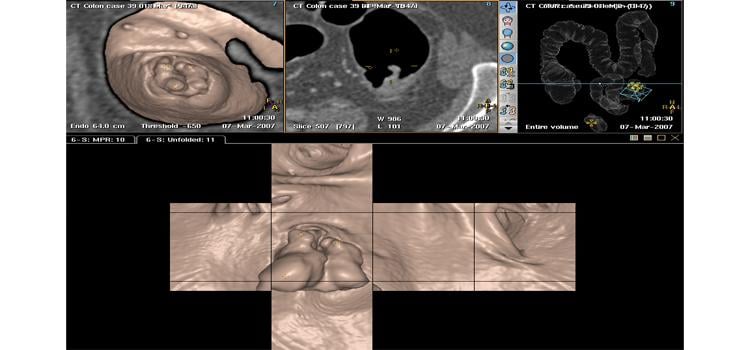

Computed tomography colonography (CTC), also known as virtual colonoscopy, offers a noninvasive alternative to ...